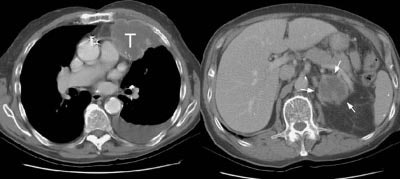

Example 2: In this patient with a T1N0 adenocarcinoma of the right lung, the staging CT scan revealed a heterogeneously enhancing mass in the left lobe of the liver (white arrows) and a low density mass in the left adrenal (yellow arrows). The liver lesion was subsequently shown to be an hemangioma and the adrenal lesion an adenoma. CT commonly detects other lesions which do not represent metastases, but which require further evaluation.

NOTE: Click image to enlarge